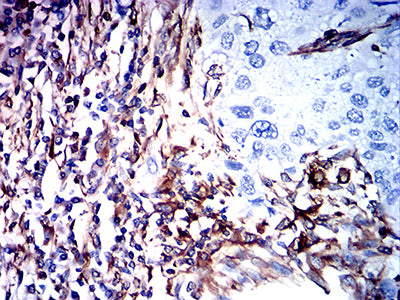

Immunohistochemical analysis of paraffin-embedded human lung cancer tissues using VIM mouse mAb with DAB staining.